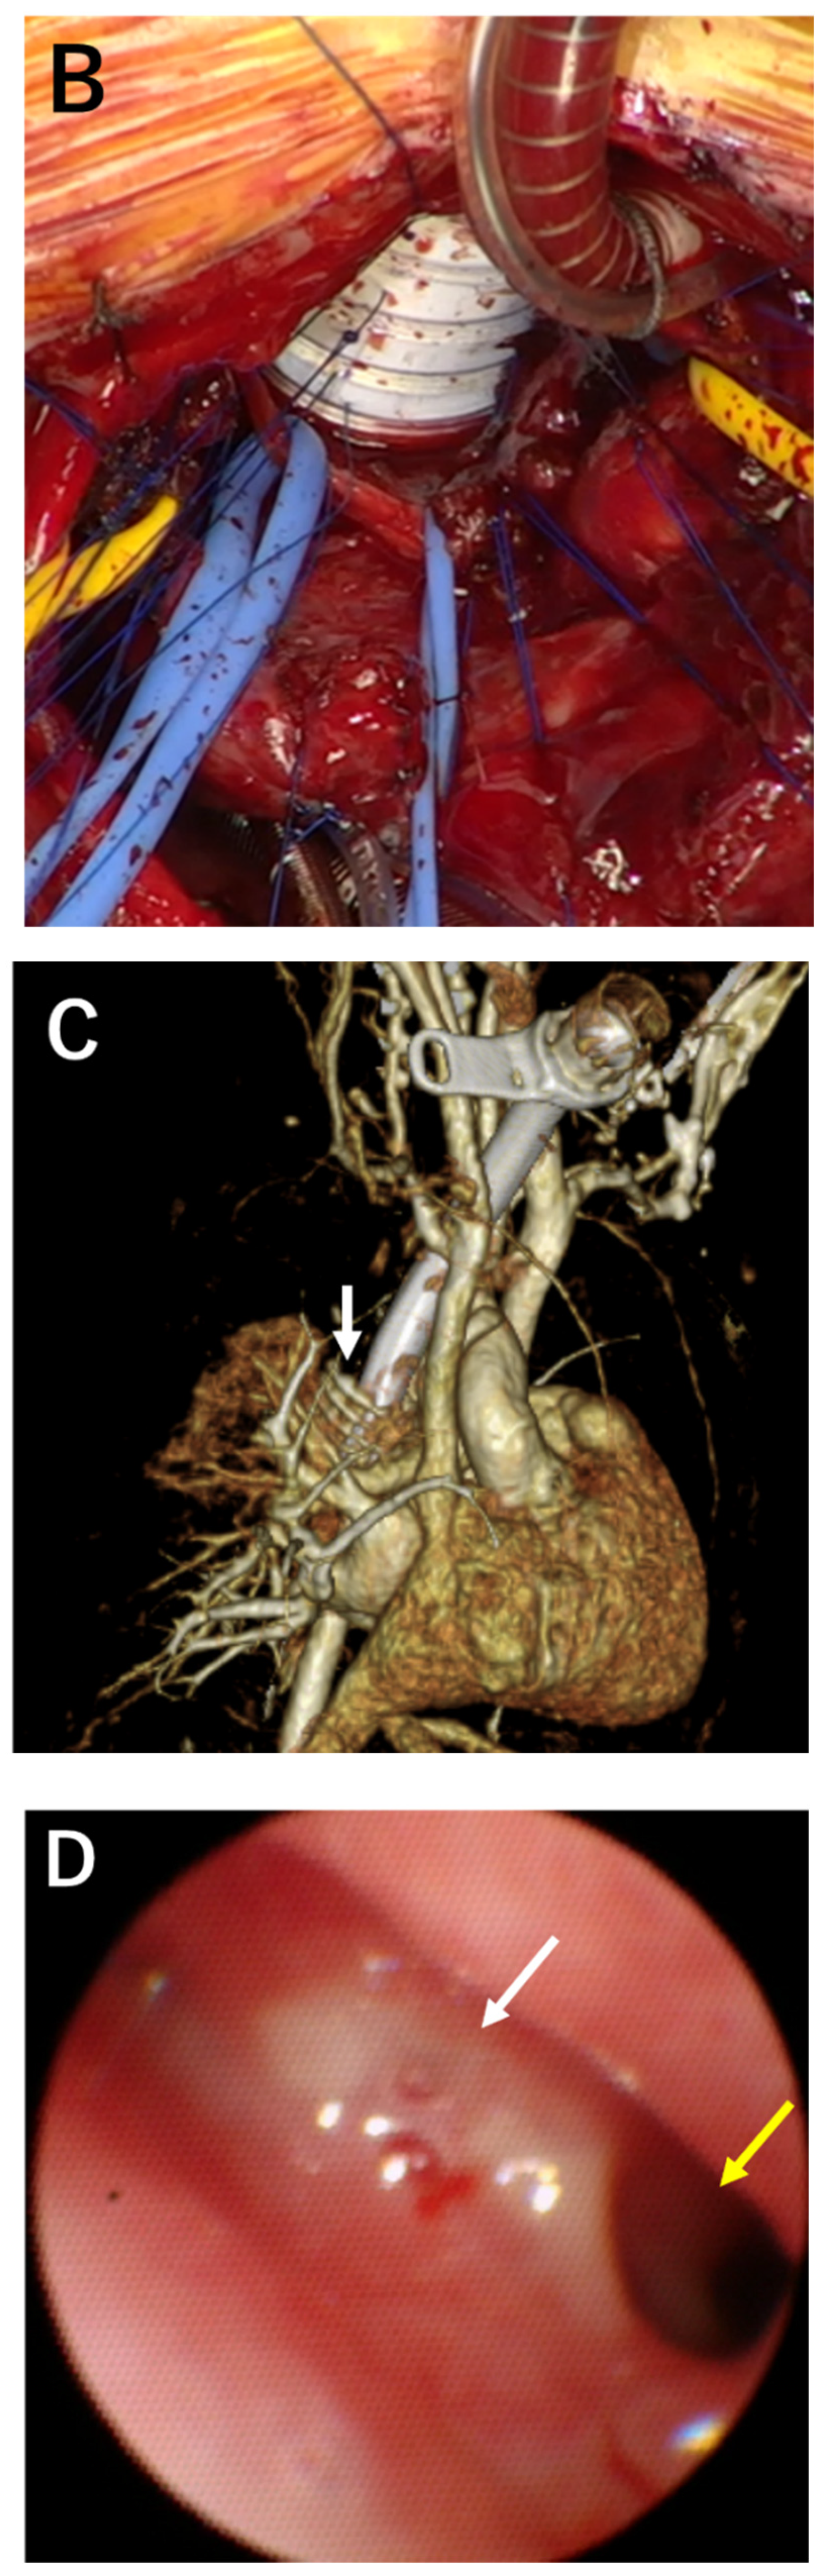

2. Case Description